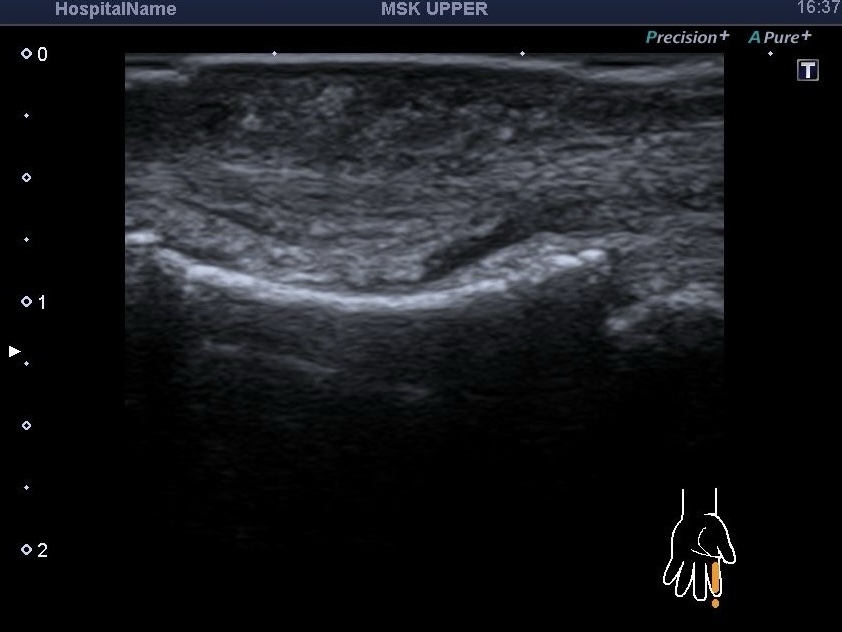

Роль УЗД у діагностиці

Під час проведення УЗД м’яких тканин пальця та кисті наші спеціалісти звернули увагу на анамнез. Після запитання про роботу з рослинами пацієнтка згадала, що нещодавно обрізала троянди на дачі.

Результати обстеження виявили:

- Виражене запалення підшкірної жирової клітковини.

- Синовіт міжфалангового суглоба.

- Теносиновіт (запалення сухожилля) згинача пальця.

- Головне — візуалізацію самого шипа в місці проколу.

При діагнозі PTS єдиним ефективним методом лікування є хірургічне втручання. Завдяки точному ультразвуковому дослідженню, лікар-діагност зробив розмітку місця залягання стороннього тіла для хірурга.